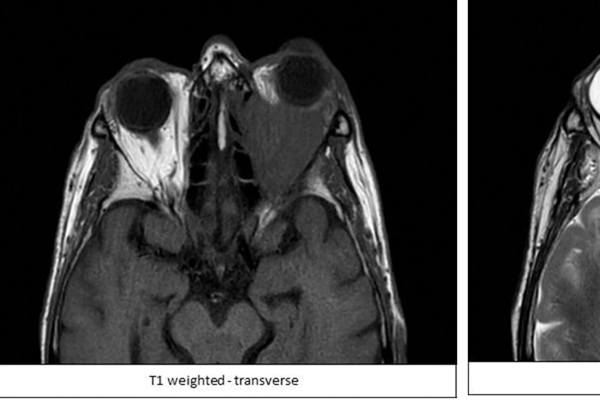

Behind the eyes: Unravelling the mystery of a painless progressive proptosis